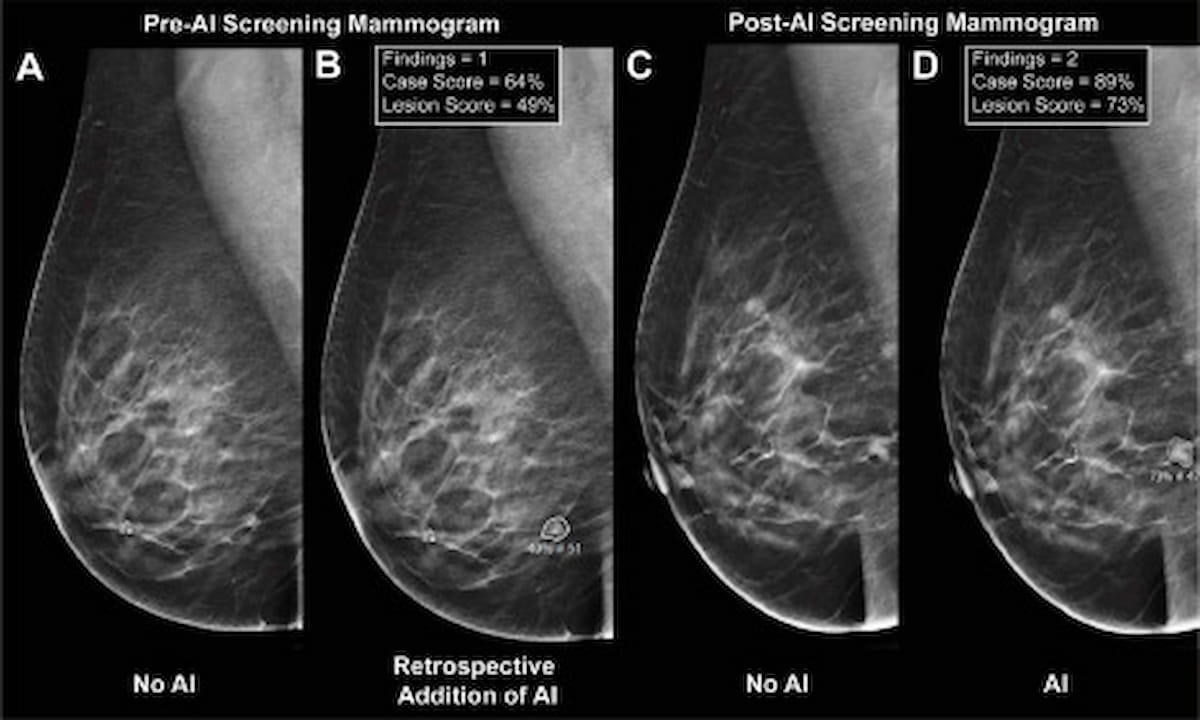

Here one can see the use of digital breast tomosynthesis (DBT) without AI (A), with retrospective application of AI (B), a screening mammogram from the post-AI cohort without AI notations (C) and a mammogram from the post-AI cohort with AI notations (D). New research revealed a higher PPV for adjunctive AI when cases proceeded to biopsy (56.5 percent vs. 32.3 percent). (Images courtesy of Clinical Breast Cancer.)

Adjunctive AI assessment of DBT offered a significantly higher PPV for AIR cases in contrast to unassisted radiologist interpretation (8.8 percent vs. 4.2 percent), according to the study findings. The researchers also noted a higher PPV for adjunctive AI when cases proceeded to biopsy (56.5 percent vs. 32.3 percent).